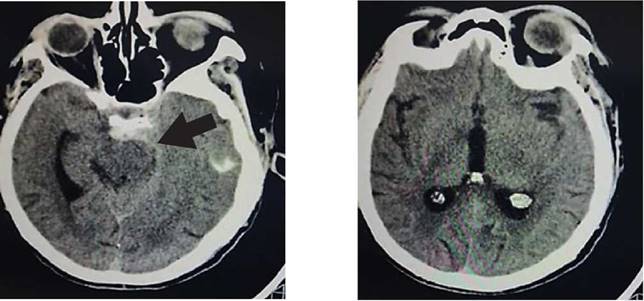

Paciente femenino de 52 años, proveniente y residente de Cochabamba, provincia Quillacollo, acude al servicio de emergencia del Hospital Obrero Nro. 2 de la Caja Nacional de Salud; con antecedentes de diabetes mellitus tipo 2, hipertensión arterial, enfermedad renal crónica, estadio 5 en hemodiálisis y un accidente cerebrovascular hemorrágico hace 1 año; es medicado con metformina 850 mg, carvedilol 12,5 mg, losartan 100 mg, alfa metildopa 500 mg y recibe hemodiálisis desde hace 1 año, trisemanal; presenta un cuadro clínico de 8 horas de evolución caracterizado por cefalea holocraneana, pulsátil, súbito, de intensidad moderada, acompañado de somnolencia, entumecimiento a nivel de columna cervical- dorsal, paraparesia de extremidades inferiores y una escala de coma de Glasgow de 11-12/15. Ingresa por emergencia en mal estado general, con tendencia a la hipertensión PA: 231/174 mmHg, PAM: 183, FC: 96 latidos/min. Saturación de oxígeno 91% aire ambiente. Se solicitan algunos laboratorios: Glicemia 380 mg/dl, creatinina 6,9 mg/dl, sodio: 129 mEq/l (Tabla 1); rápidamente se solicita una tomografía axial computarizada de cráneo (TAC) simple (Figura 1a, b).

Figura 1a, b: TAC de cráneo simple: sin desviación de la línea media, cisternas ventriculares conservadas con imagen hiperdensa en cisterna peritroncal (flecha negra), no se observa lesiones intraparenquimatosas.